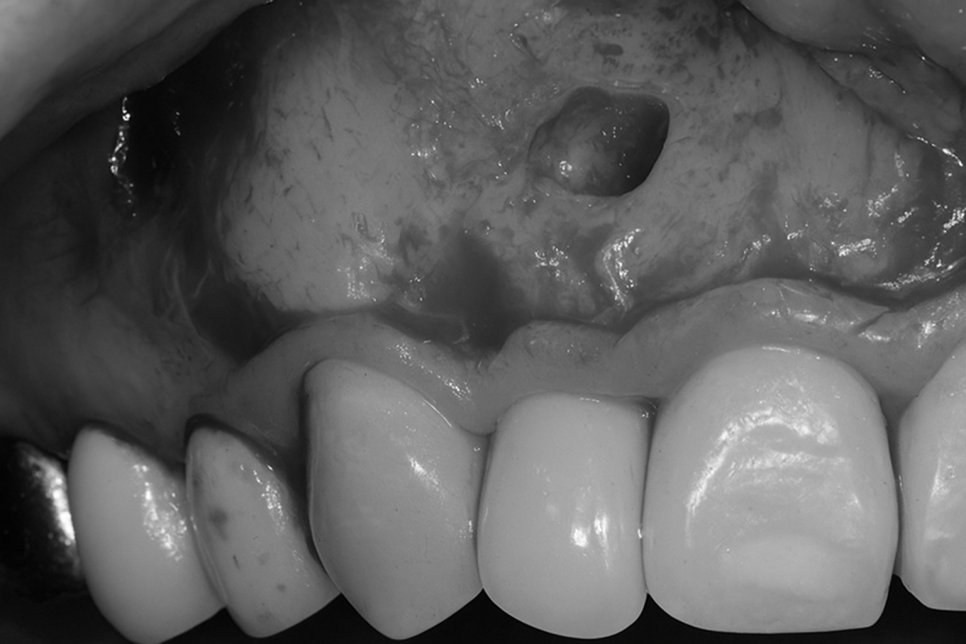

염증을 긁어내 깨끗한 환경이 조성되어

점차 치유되면 당산동 치과 사진처럼

잇몸 여드름이 사라지고 다시 안정된

상태를 보여주게 됩니다.